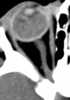

Globe calcification

Intraorbital calcification